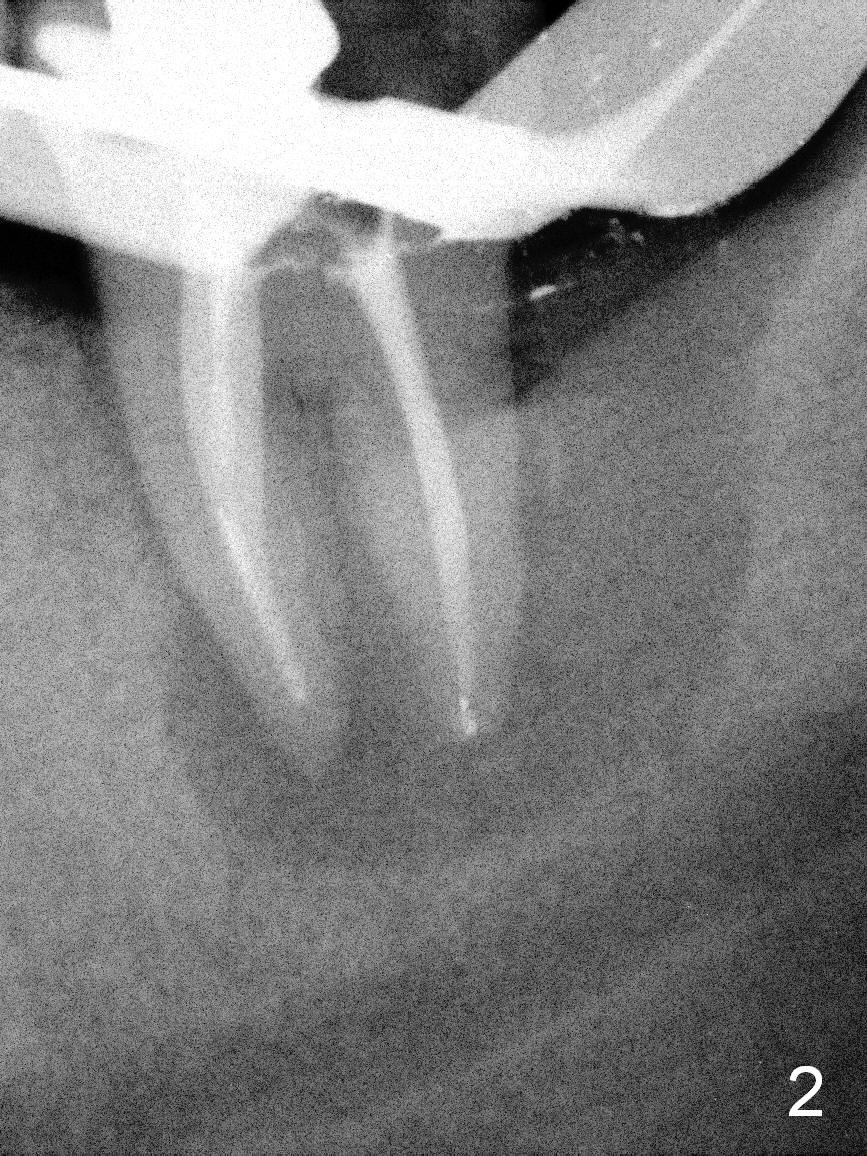

A 55-year-old man must be a dental phobic. With a fistula (Fig.1 <) and large radiolucency associated with the lower left 2nd molar, he postponed root canal therapy for 2 years and 8 months (Fig.2). Later he refused to have crown for the tooth. Three years and 5 months later, the radiolucency seems to have been resolved (Fig.3), but the tooth has fractured with buccal infection. The patient is unwilling to accept treatment of extraction (no antibiotic socket treatment) and immediate implant (Fig.4).